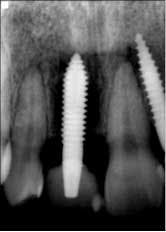

Implant sites were curetted well, then disinfected with Chloramine-T saturated gauze, followed by irrigation with 2% chlorhexidine and water. Bone grafting was not deemed necessary. Both implants No. 8 and No. 10 were replaced with TRX-OP 4.5 x 13 mm (Fig. 5). The patient was informed that because implants placed into previously failed sites have a lower success rate, absolute adherence to postoperative instructions was critical to any chance of success (4). Instructions were once again given to follow dietary restrictions and take the antibiotics as prescribed. The patient was seen six weeks postoperatively (Fig. 6) and set to have the final prosthesis inserted six months post-reimplantation.Fig. 5: No. 8 and No. 10 — implants replaced by 4.5 x 13 mm and retemporized.